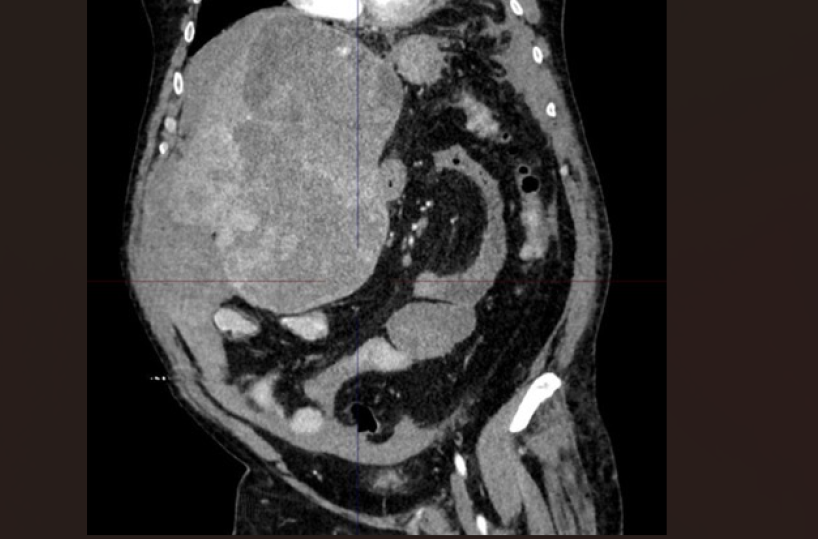

Chirurgia epatica estrema al Policlinico di Bari per l’asportazione di un tumore di quasi 5 kg e 30 cm di diametro, che occupava più della metà dell’addome in un paziente di 60 anni. Un caso di estrema complessità, giunto in urgenza con un’emorragia epatica in atto, che ha richiesto il coinvolgimento di equipe multidisciplinari per salvare la vita del paziente.